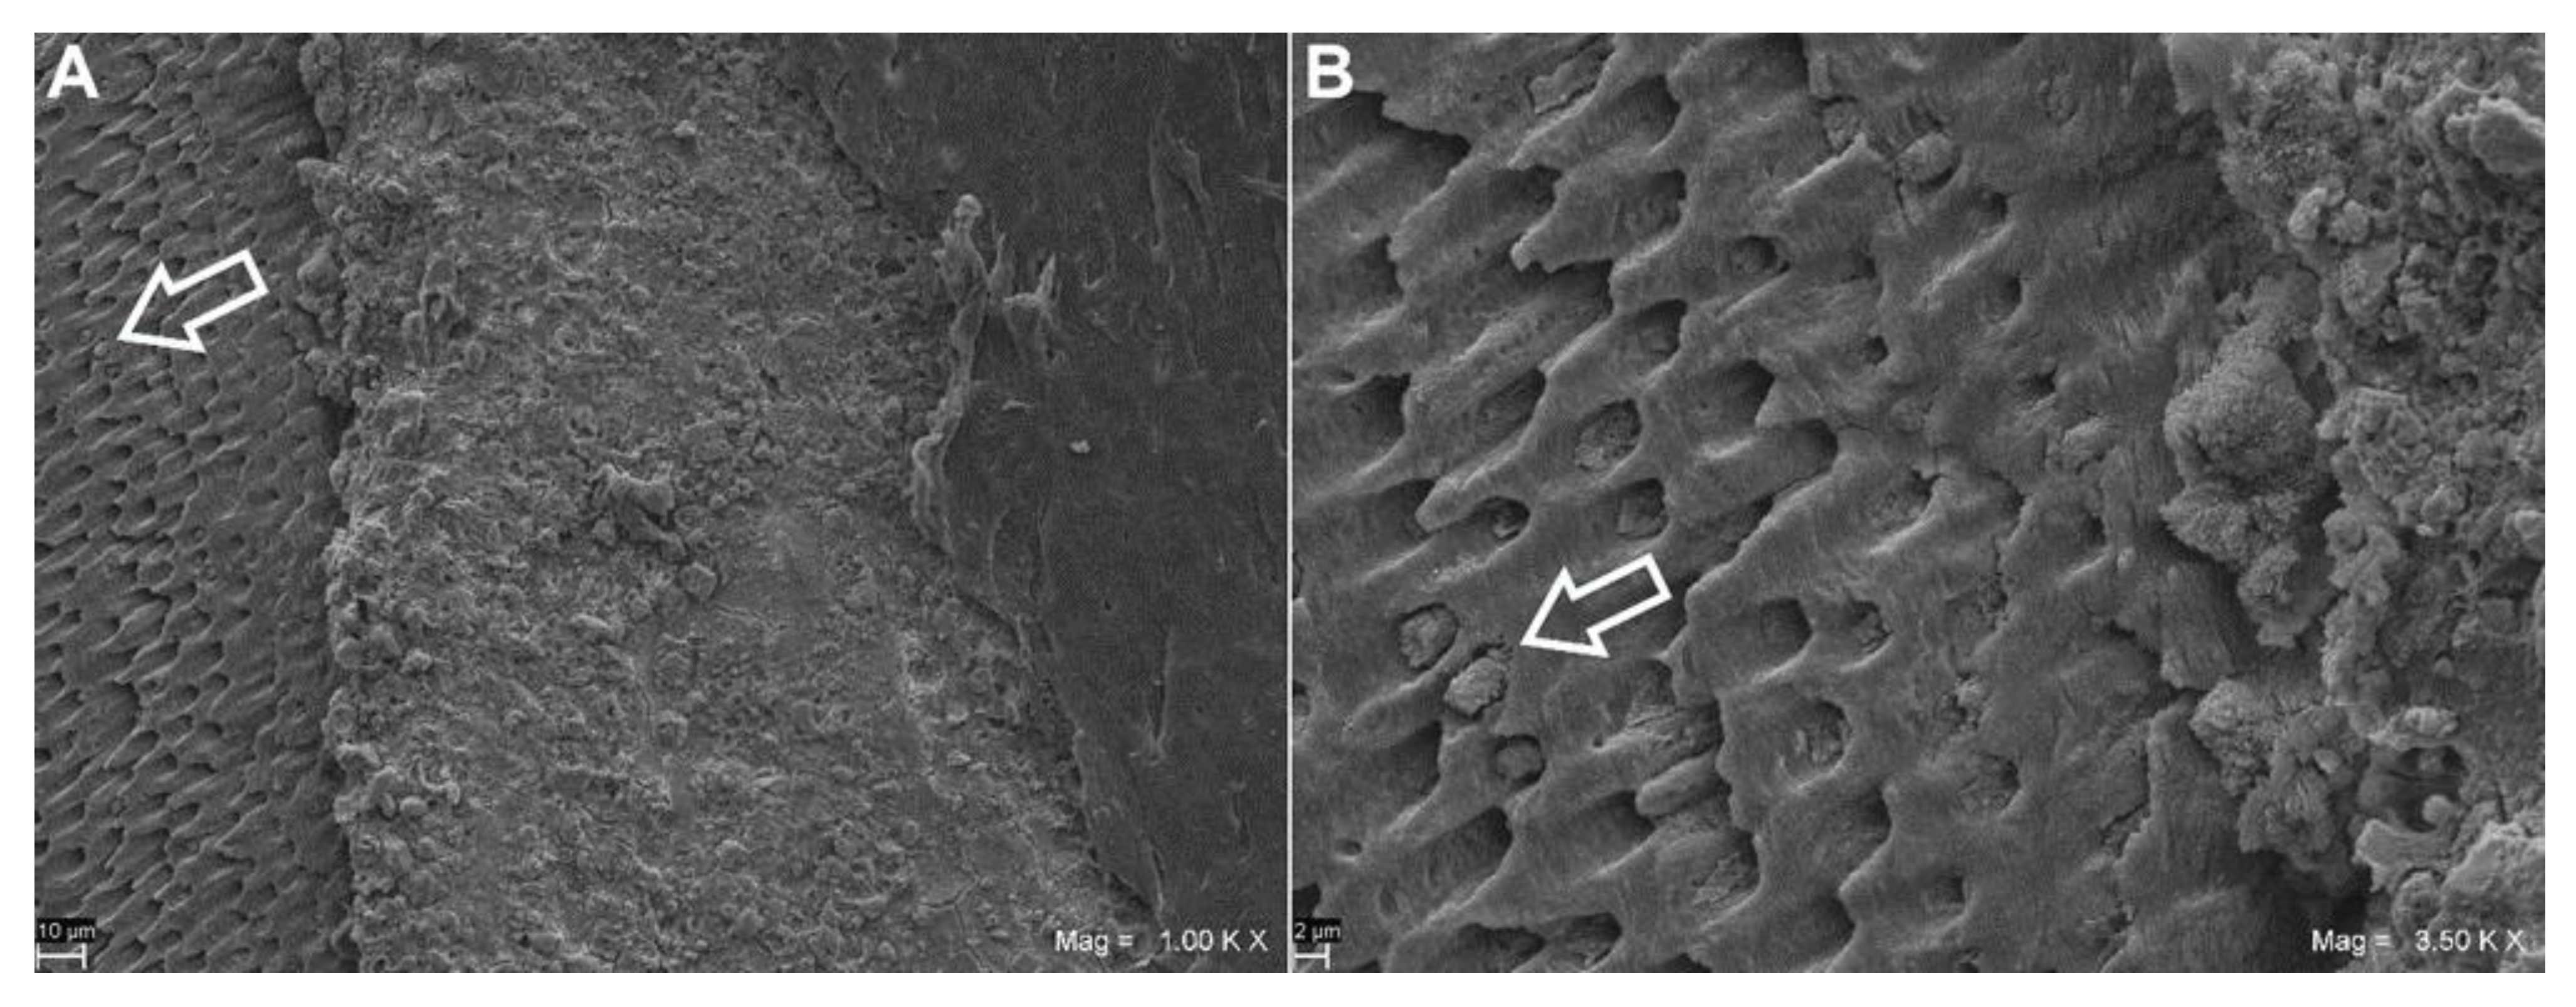

- Moura-Netto, C.; Guglielmi Cde, A.; Mello-Moura, A.C.; Palo, R.M.; Raggio, D.P.; Caldeira, C.L. Nd: YAG laser irradiation effect on apical intracanal dentin—A microleakage and SEM evaluation. Braz. Dent. J. 2011, 22, 377–381. [Google Scholar] [CrossRef][Green Version]